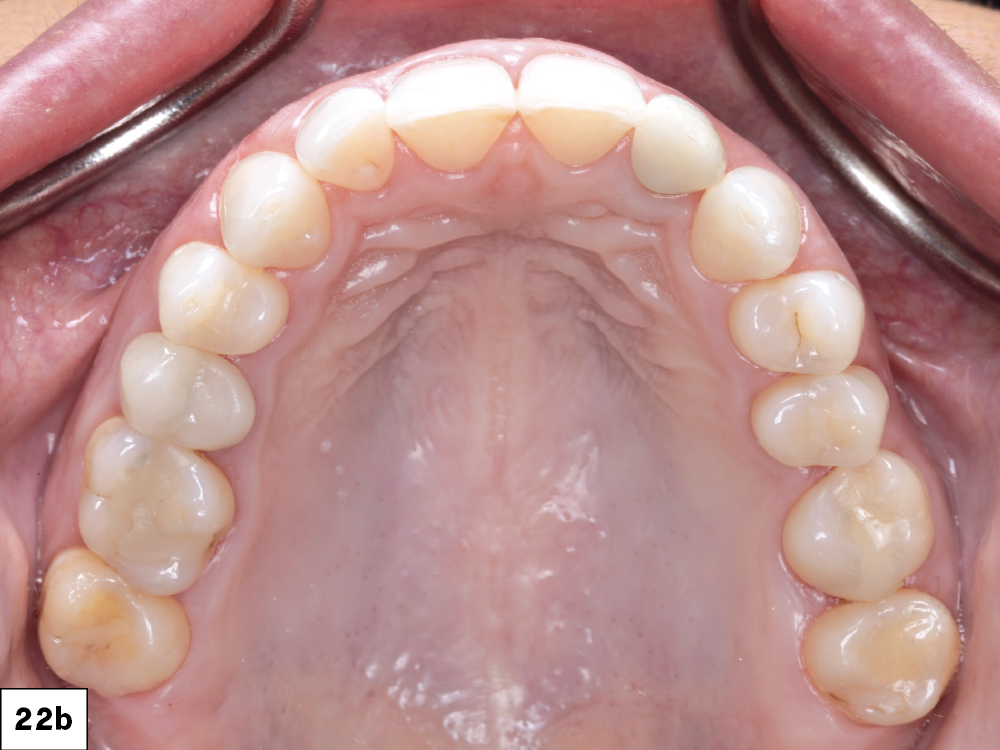

Figures 22a–22c: The Glidewell HT implant, custom hybrid abutment, and BruxZir Esthetic cement-retained restoration were successfully delivered without compromising the hard- or soft-tissue contours. To protect against further damage to the teeth and the newly placed implant, an occlusal guard was prescribed.